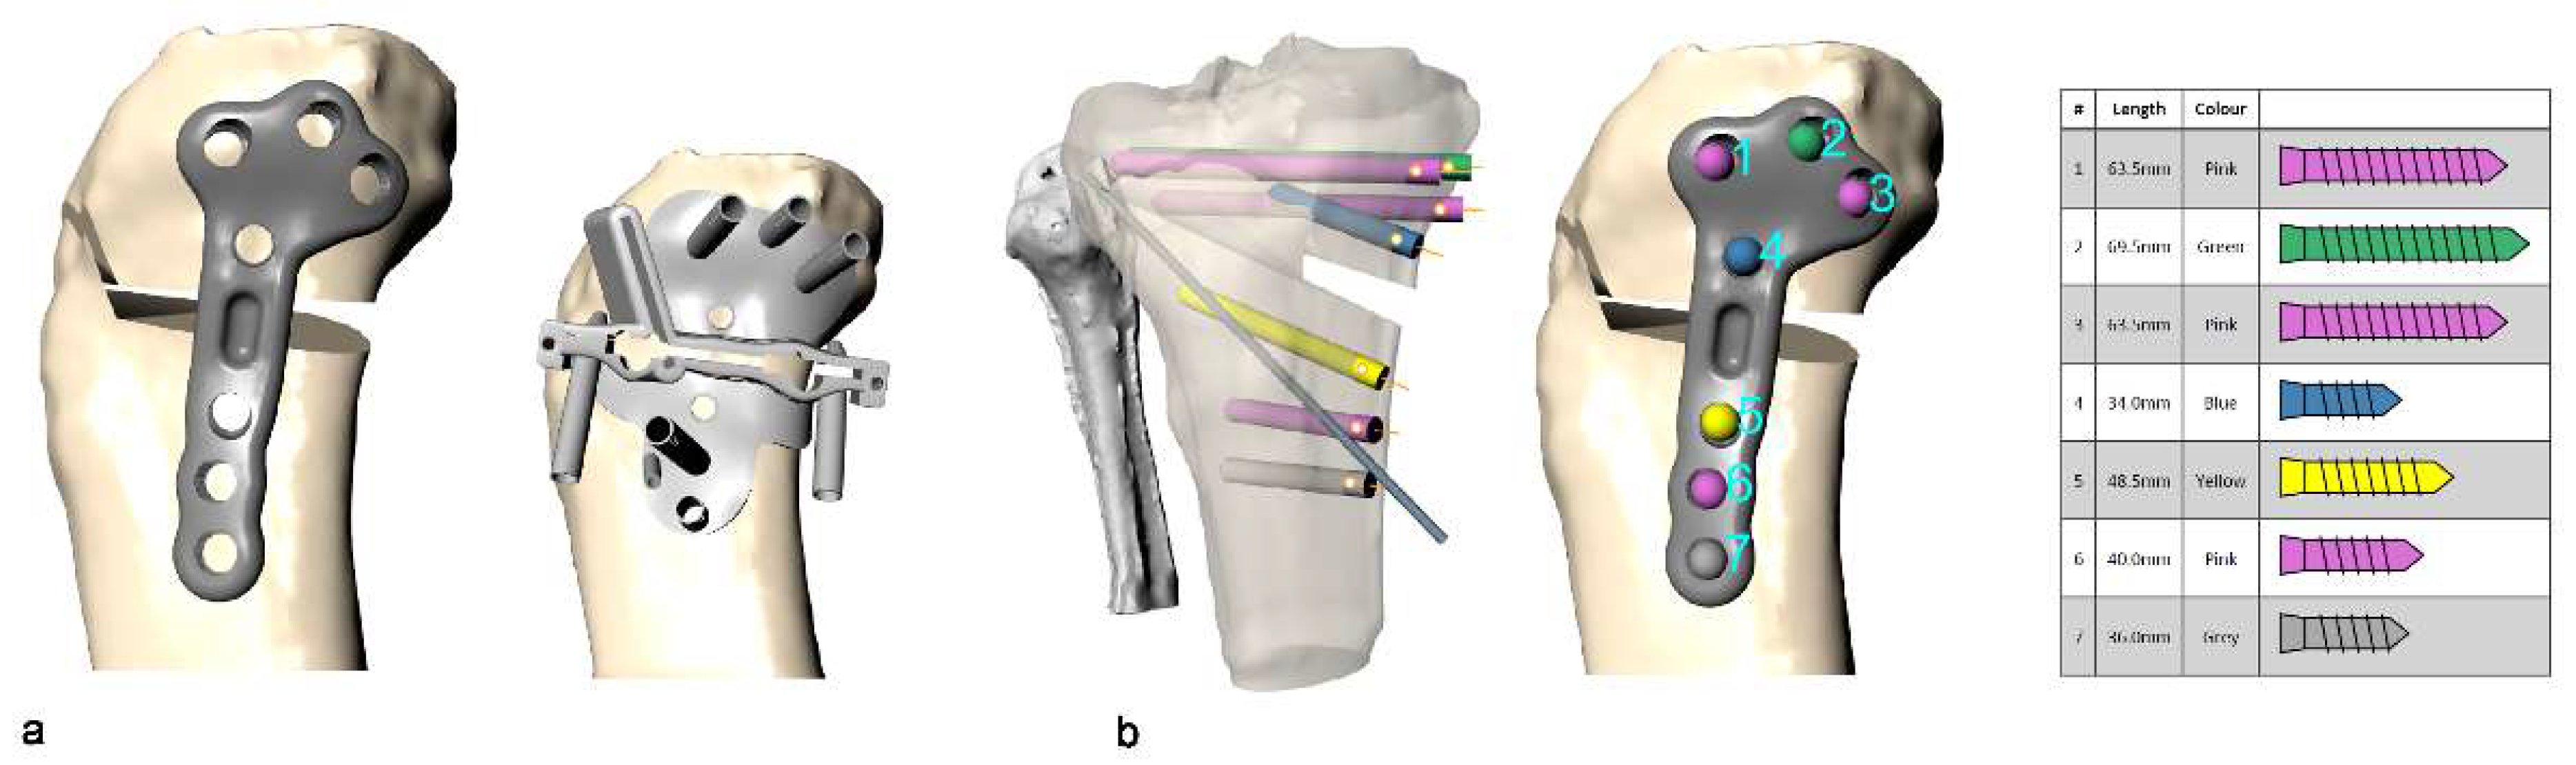

4.2. Customized System for Valgus HTO

4.3. Surgical Technique